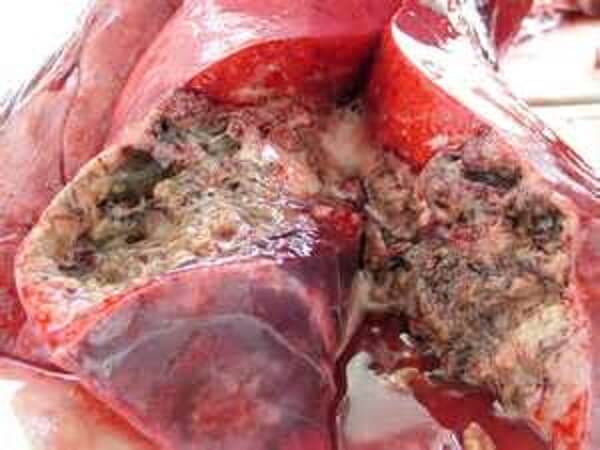

იცით რამდენი ადამიანი გარდაიცვალა სოკოვანი ინფექციით 2023 წელს? გასულ წელს საქართველოში 55 000 ადამიანი დაიღუპა. მათგან 31 000-ს ფეხის სოკო ჰქონდა. ეს მაჩვენებელი ყველა დაღუპულთა ნახევარზე მეტს შეესაბამება. ფრჩხილის სოკო არა მხოლოდ ფეხის ფრჩხილებს აზიანებს, არამედ შედის სისხლში და ვრცელდება ტერფებით მთელ სხეულზე. სოკო ანადგურებს ჩვენს სხეულს შიგნიდან და იწვევს სტრესს ყველა ორგანოში. მცირე სპორები ემაგრება შინაგან ორგანოებს და მრავლდება, რაც იწვევს სხვადასხვა სახის დაზიანებას. ამიტომ სოკოვანი ინფექციით ზიანდება შინაგანი ორგანოებიც. ეს ნიშნავს, რომ სხეული შიგნიდან "ლპება". დროთა განმავლობაში შეიძლება გული გაუმართოს, თავის ტვინში სისხლძარღვი გასკდეს ან განვითარდეს ღვიძლის კიბო. ასევე შესაძლებელია თირკმლის უკმარისობა. ყველას, ვისაც ფრჩხილის სოკო აწუხებს, რისკის ქვეშ იმყოფება. იმუნური სისტემა დასუსტებულია ხშირი გაციების გამო და სტრესი დანარჩენს აკეთებს, რაც იწვევს უეცარ სიკვდილს.

შედეგად, დაზარალებულები იღუპებიან სისხლის მოწამვლის ან შინაგანი ორგანოების უკმარისობის შედეგად. არც კერძო კლინიკებშია უკეთესი მდგომარეობა. ისინი ხშირად ასაქმებენ გამოუცდელ ექიმებს, რომლებმაც ცოტა რამ იციან დაავადებებისა და მათი მკურნალობის მეთოდების შესახებ. მათი მიზანი მხოლოდ პაციენტებისგან რაც შეიძლება მეტი ფულის მიღებაა და გრძელვადიან პერსპექტივაში პაციენტების დახმარების გაწევის ინტერესი არ აქვთ.